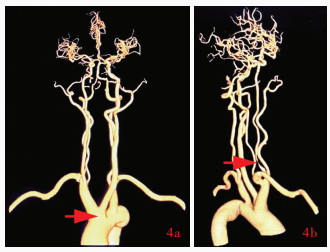

Cheng P , Liu BL , Zhao BB , Yu DL . The utilization of carotid artery ultrasound in diagnosis of internal carotid artery absence and its imaging features. Zhongguo Xian Dai Shen Jing Ji Bing Za Zhi, 2023, 23: 933- 939.

doi: 10.3969/j.issn.1672-6731.2023.10.011

程盼, 刘保龙, 赵碧波, 于德林. 颈内动脉缺如超声诊断要点及其他影像学特点分析. 中国现代神经疾病杂志, 2023, 23: 933- 939.